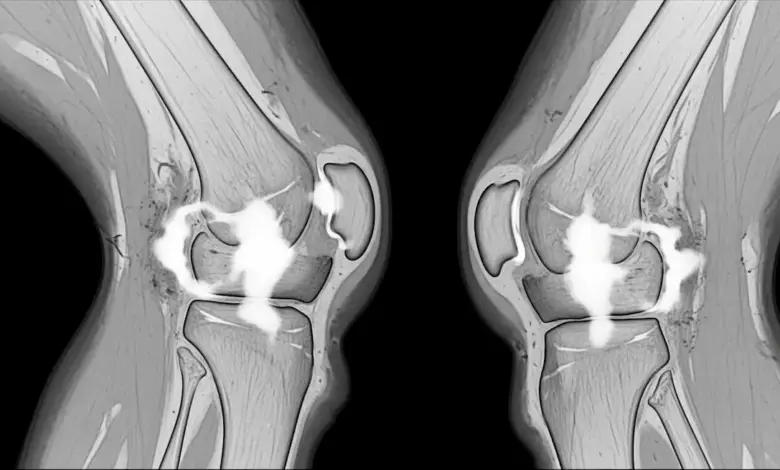

O edema ao redor de um ligamento representa acúmulo de líquido e alteração inflamatória nos tecidos vizinhos, que pode aparecer após torções, impactos, movimentos bruscos ou sobrecarga repetitiva.

Em alguns casos, o ligamento permanece íntegro e o edema reflete apenas uma agressão local. Em outros, o exame pode estar mostrando a repercussão de uma lesão parcial ou completa.

No joelho, esse tipo de alteração pode estar próximo de estruturas como:

- Ligamento colateral medial;

- Ligamento colateral lateral;

- Ligamento cruzado anterior;

- Ligamento cruzado posterior;

- Complexo capsuloligamentar;

O ponto mais importante é entender qual estrutura está envolvida e se existe comprometimento funcional.